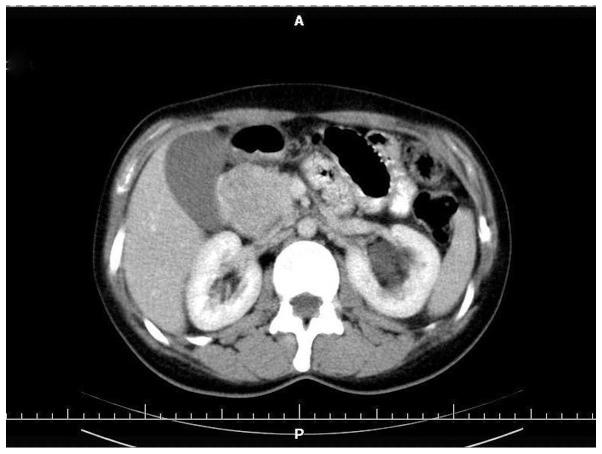

Neuroendocrine tumors constitute a group of heterogeneous neoplasms, both those that are clinically asymptomatic and those which present with an array of symptoms. This variable clinical manifestation and unsatisfactory detection rate on diagnostic imaging make preoperative diagnosis particularly challenging. Insulinoma is a rare tumor originating from insulin-synthetizing pancreatic beta cells which clinically manifests hypoglycemia. The current study presents the case of a patient with a one month history of diabetes, and a tumor of the pancreatic head diagnosed at the Regional Hospital of Lomza (Lomza, Poland). The patient subsequently underwent surgery. The histological examination indicated insulinoma; islet cell tumor of the pancreas. The patient's postoperative period was uneventful and during two years of follow-up, the patient has remained in good health with completely controlled diabetes mellitus. The hereby-presented case of pancreatic insulinoma confirms this finding, as a correct diagnosis could only be established on the basis of pathomorphological examination. In addition, radical surgical resection is currently the only available treatment.

神经内分泌肿瘤是一组异质性肿瘤,包括临床无症状的肿瘤和表现出一系列症状的肿瘤。这种多变的临床表现以及诊断性影像学检查中不尽人意的检出率使得术前诊断极具挑战性。胰岛素瘤是一种罕见的肿瘤,起源于合成胰岛素的胰腺β细胞,临床上表现为低血糖。本研究报告了一例患者,该患者有1个月的糖尿病病史,在波兰洛姆扎地区医院被诊断为胰头肿瘤。该患者随后接受了手术。组织学检查显示为胰岛素瘤;胰腺胰岛细胞瘤。患者术后恢复顺利,在两年的随访期间,患者健康状况良好,糖尿病得到完全控制。此处报告的胰腺胰岛素瘤病例证实了这一发现,因为只有通过病理形态学检查才能做出正确诊断。此外,根治性手术切除目前是唯一可行的治疗方法。